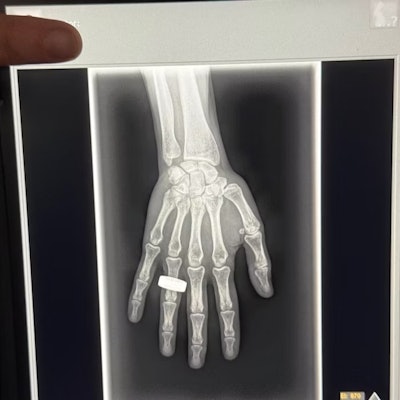

Best Radiology Image

First x-ray image taken in space. Image from Chun Wang, et al.

The first finalist for Best Radiology Image is out of this world -- literally, it is the first x-ray taken in space.

The image was acquired during the Fram2 space mission led by 42-year-old cryptocurrency entrepreneur Chun Wang. The mission launched on March 31 from NASA’s Kennedy Space Center in Florida. On April 1, the all-civilian crew woke up, had breakfast, and “took a few x-ray images,” Wang wrote in a post on the social media platform X.

Sharp observers will note that the image bears a resemblance to the first x-ray ever taken by Wilhelm Roentgen of his wife Anna Bertha Ludwig's hand on December 22, 1895.

That was intentional.

“The crew members were informed of Wilhelm Roentgen’s first x-ray image and were excited to honor that pioneering achievement 129 years later by recreating the image in space,” said Jeanne Walter, vice president of marketing and sales for MinXray, the company that manufactured the portable x-ray machine used to acquire the image.

An analysis of the acquired data and images is still underway, and findings will be shared once the research is complete, Walter added.